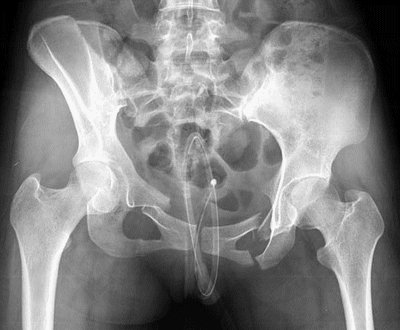

Лечение проводится в стационаре. Терапия на дому не дает ожидаемого результата и может ухудшить состояние пациента. Программа лечения разрабатывается на основе диагностики, которая включает:

- внешний осмотр;

- рентгенографию;

- компьютерную томографию.